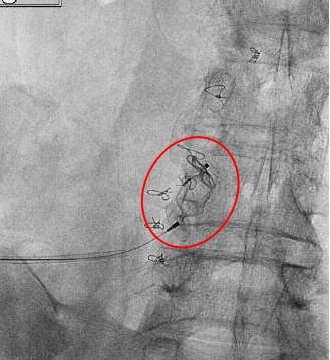

PARTO Plug-assisted Retrograde Transvenous Obliteration (PARTO) 为什么PARTO? PARTO是对BRTO的改进。和CARTO一样,PARTO这一技术应用血管塞和明胶海绵栓塞,没有硬化剂使用安全性高,并发症相对少。避免了硬化剂迁移,没有肺动脉拴塞的风险,也不用担心硬化剂导致的血尿和肾功能不全。所以为什么不用BRTO是因为它的并发症。另外,PARTO整个操作胶BRTO节省时间,用弹簧栓子栓塞其它输入血管可能没有必要 ![]() 病例一

明胶海绵注射